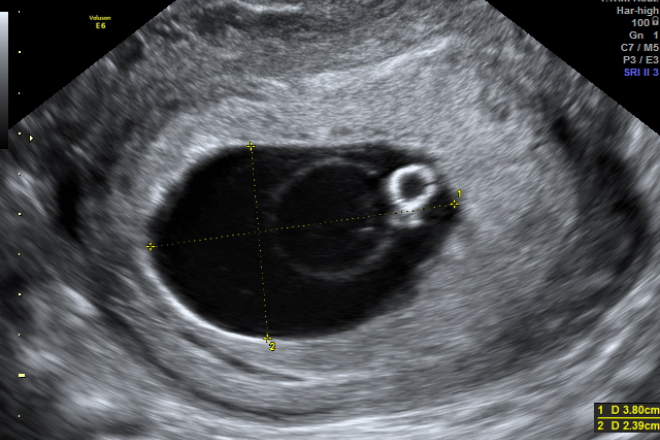

El objetivo de este estudio es evaluar la fiabilidad de las mediciones clínicas, ultrasonográficas y una nueva fórmula en la estimación del peso fetal durante la fase activa del trabajo de parto, con el fin de determinar cuál es el más preciso. La fórmula clínica utilizada para la comparación fue la de Johnson para fetos libres (altura del fondo uterino – 11 x 155) y para fetos encajados (altura del fondo uterino – 12 x 155). Se realizaron mediciones ultrasonográficas para estimar el peso fetal mediante la fórmula de Hadlock. Se monitoreó el trabajo de parto hasta el parto, y el peso en gramos de los recién nacidos se obtuvo en los primeros cinco minutos de vida extrauterina.

La inclusión de la técnica 3D en ultrasonografía ha permitido una visualización más detallada del feto, mejorando la evaluación de su compleja estructura y entorno variable. La imagen 3D se obtiene mediante la adquisición de múltiples cortes paralelos a través del movimiento de un transductor de ultrasonido. La representación en 4D, que muestra imágenes en movimiento, constituye el avance más reciente en esta tecnología. Aunque el ultrasonido 3D ofrece numerosas ventajas, como la posibilidad de análisis multiplanar de un volumen específico, presenta limitaciones como el elevado costo de los equipos y dificultades asociadas a movimientos fetales o posición fetal inadecuada.